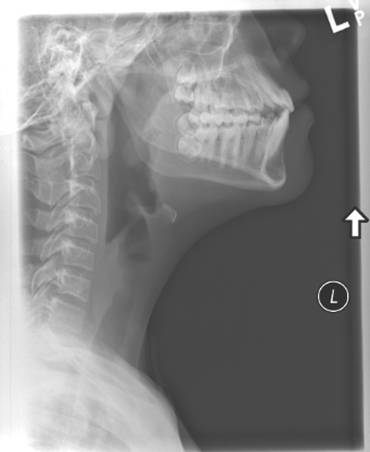

A soft tissue neck x-ray was ordered in the Emergency department.

PLEASE DESCRIBE THE X-RAY?